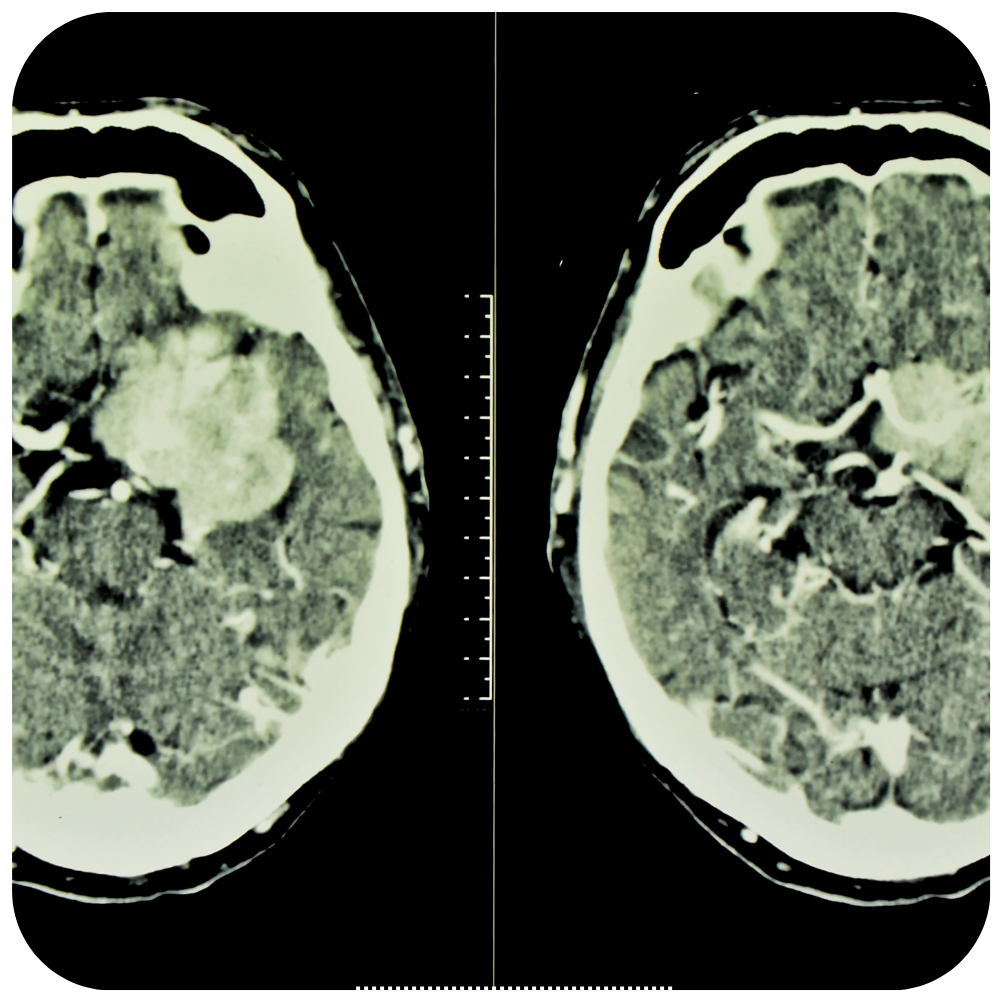

Craneotomía Operación en la que se extrae un pedazo del cráneo. Una craneotomía se realiza para que los médicos puedan extraer un tumor o tejido anormal del cerebro. También se puede realizar para extraer sangre o coágulos del cerebro, aliviar la presión en el cerebro después de una lesión o…